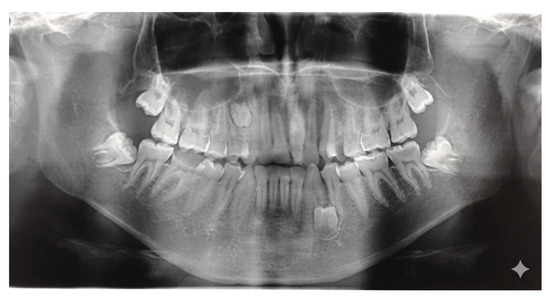

Background: Supernumerary teeth (ST) are developmental anomalies that may interfere with eruption, alignment, and occlusal balance. Their etiopathogenesis and management remain controversial. This multicentric study aimed to evaluate the epidemiological, morphological, and radiographic features of ST in a Romanian population and identify impact predictors. Methods: Between January 2020 and March 2025, 153 consecutive patients (91 males, 62 females; mean age 14.8 ± 6.2 years) with clinically and radiographically confirmed supernumerary teeth were evaluated across three Romanian academic centers: the University Dental Clinic, George Emil Palade University of Medicine, Târgu Mureș (n = 78 patients); the Department of Periodontology, Lucian Blaga University of Sibiu (n = 45 patients); and the Department of Dentistry, Dimitrie Cantemir University of Târgu Mureș (n = 30 patients). Results: A total of 185 ST were recorded, most frequently conical (48.6%) and mesiodens (56.2%). Complications were observed in 40.5% of patients. Multivariable analysis identified Angle Class III malocclusion (OR = 1.89; p = 0.039) and tuberculate morphology (OR = 2.93; p = 0.021) as the strongest independent predictors of impaction, alongside associations with younger age (<13 years) (OR = 3.12; p = 0.003) and male gender (OR = 1.78; p = 0.046). CBCT demonstrated high diagnostic concordance with OPG (κ = 0.89), but showed superior performance for complex cases, identifying 11 root resorptions and 9 vestibulo-palatal displacements that OPG missed. Multivariable analysis identified Angle Class III malocclusion (OR = 1.89; p = 0.039) and tuberculate morphology (OR = 2.93; p = 0.021) as the strongest independent predictors of impaction, alongside associations with younger age (<13 years) (OR = 3.12; p = 0.003) and male gender (OR = 1.78; p = 0.046). Conclusions: This multicentric study provides updated Romanian data and highlights novel risk factors and diagnostic selection guidelines that may support individualized treatment planning. Angle Class III malocclusion is a novel and critical independent predictor of supernumerary tooth impaction, alongside tuberculate morphology. This finding strengthens the rationale for utilizing CBCT specifically in Class III patients with ST to pre-emptively manage complex impactions and associated pathology. Full article

Figure 1